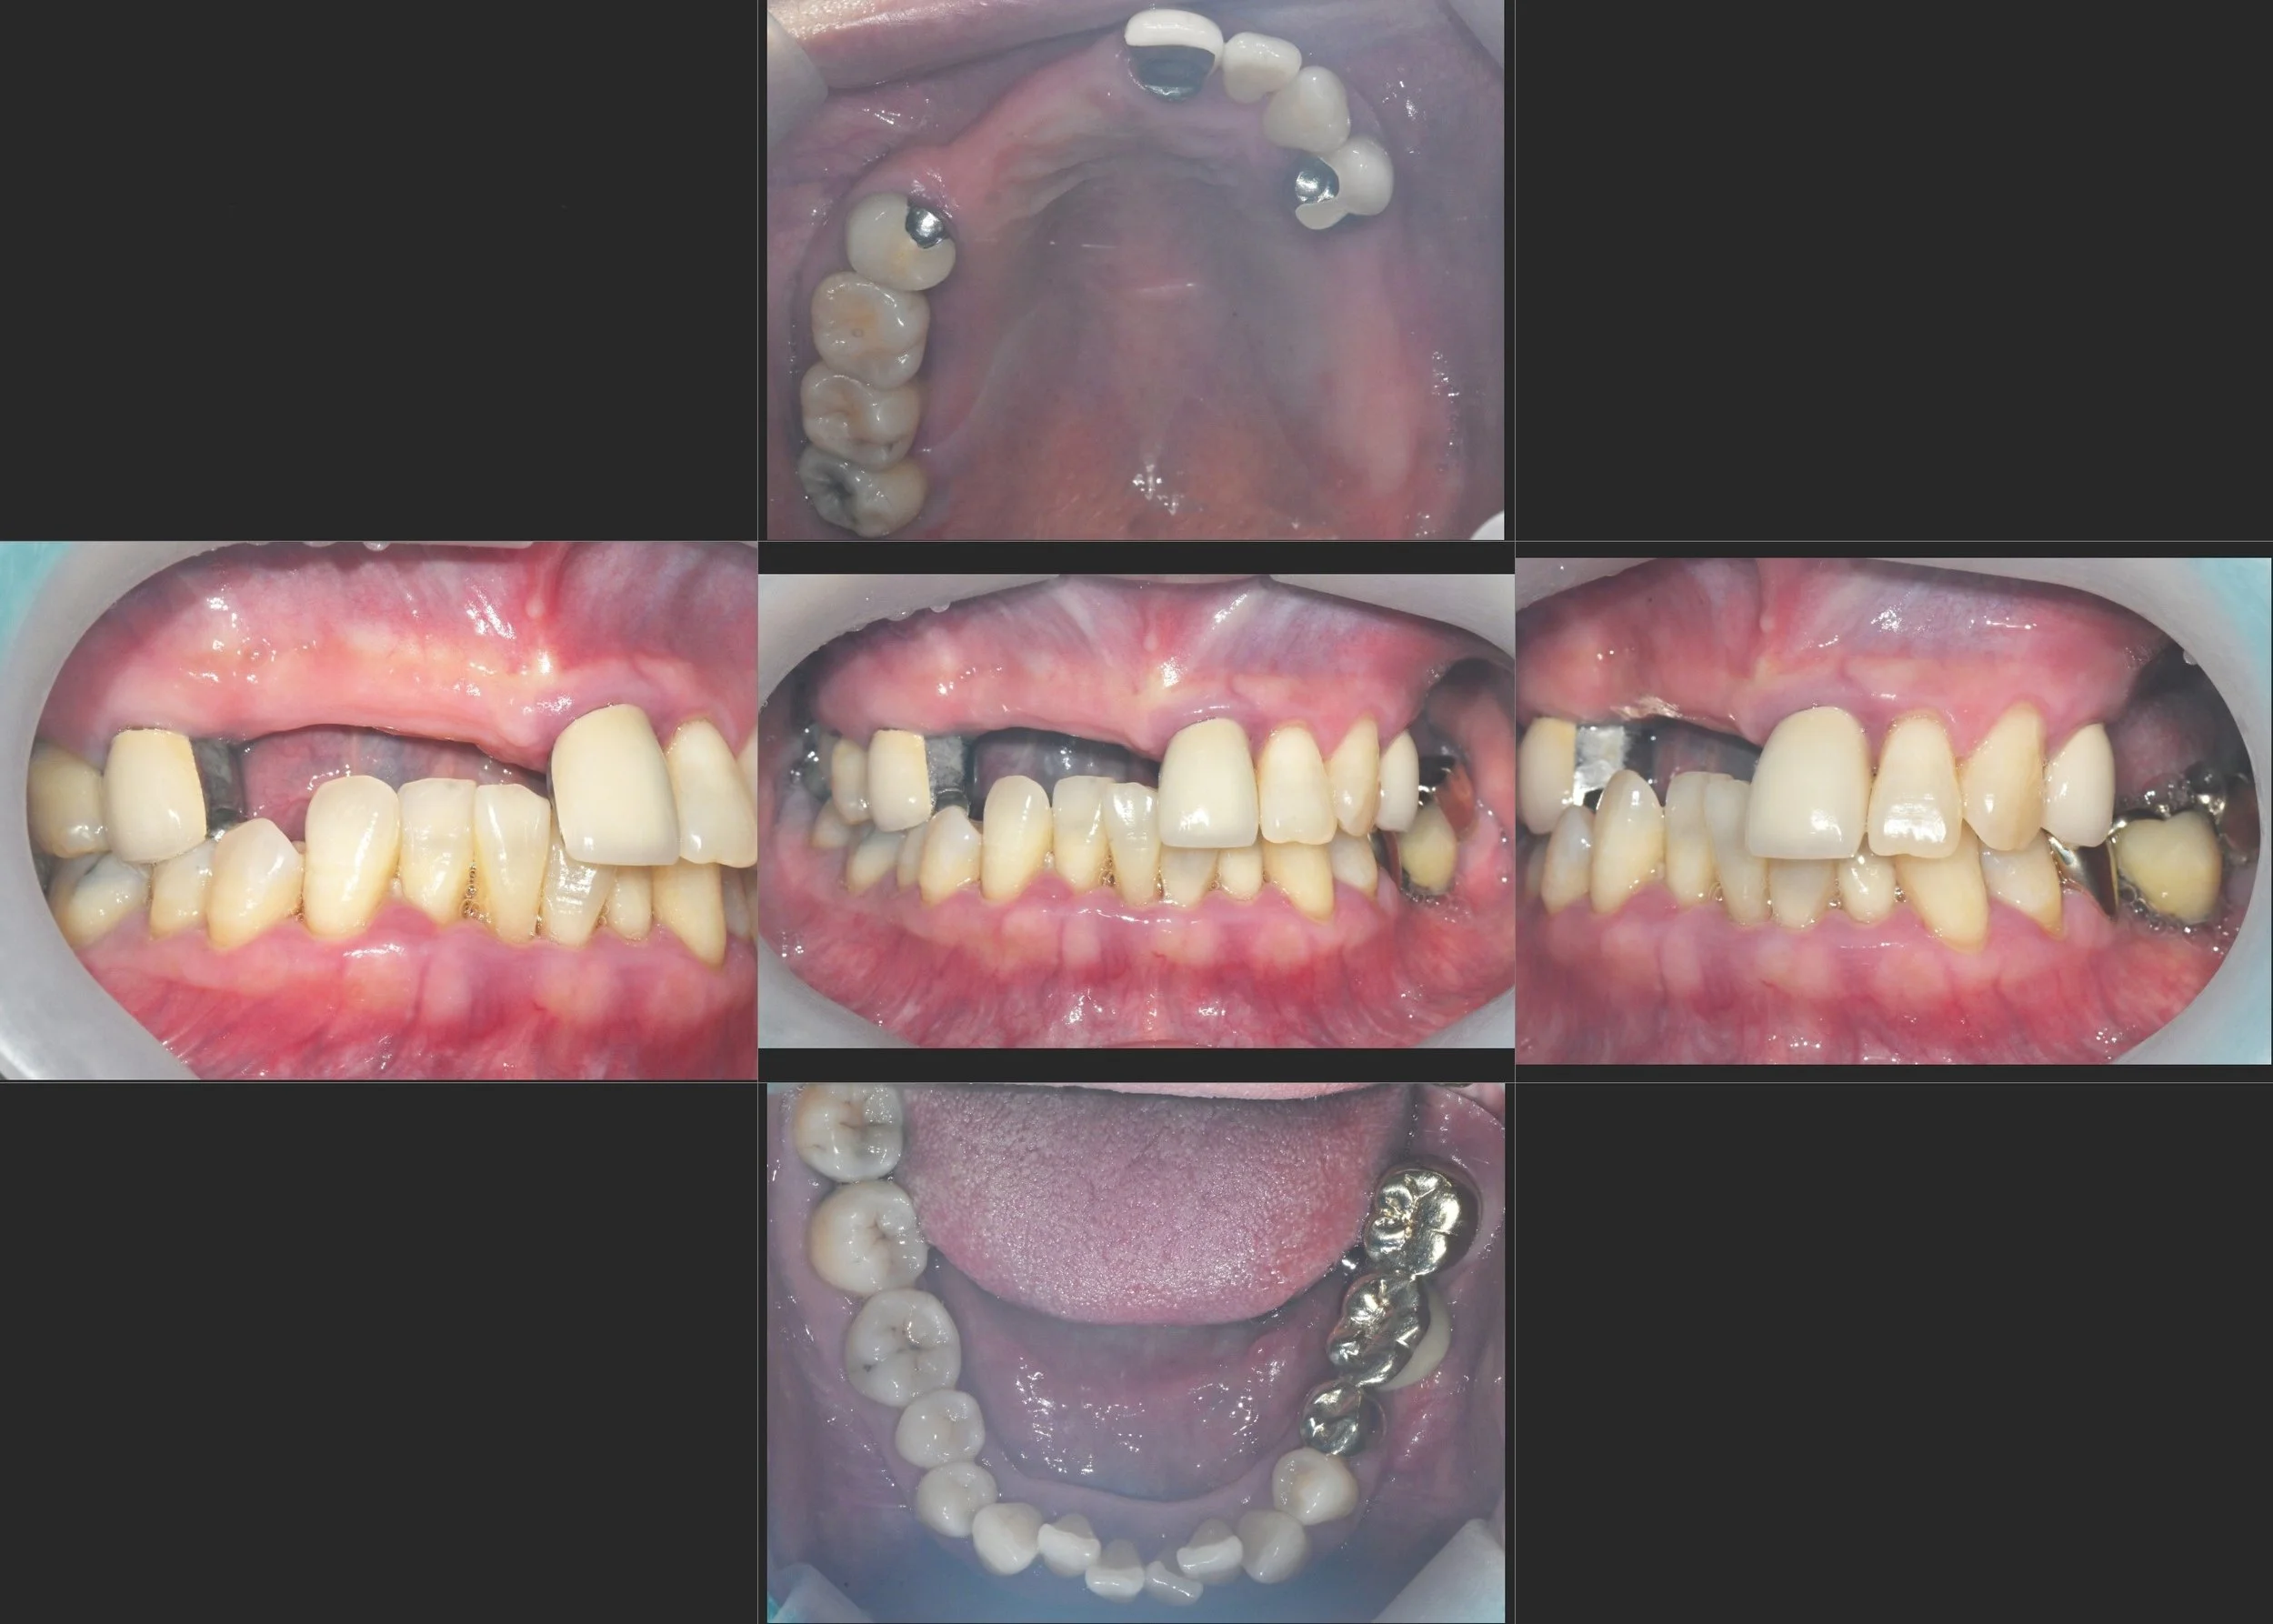

INTRA ORAL - AFTER

4. Definitive Delivery: Final zirconia bridges and crowns were delivered. The occlusal scheme was meticulously calibrated to provide stable stops and interference-free guidance, ensuring a seamless transition when the patient is ready for the final phase of her full-mouth journey.

The result is a functional and aesthetic transformation that respects the patient's pacing while providing the clinical stability required for long-term success.